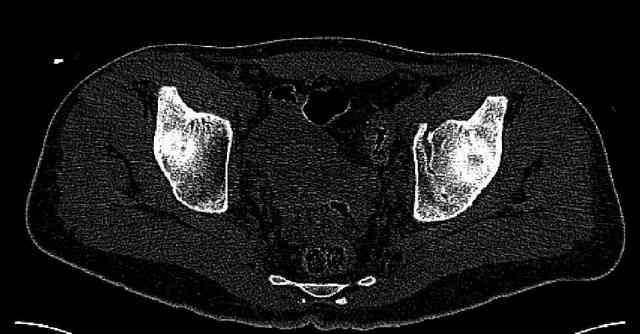

Some more images. Does it help to guess which part of the acetabulum is displaced?

Normal appearing SI joints and a healed posterior column limb... my bet's on caudal segment displacement.